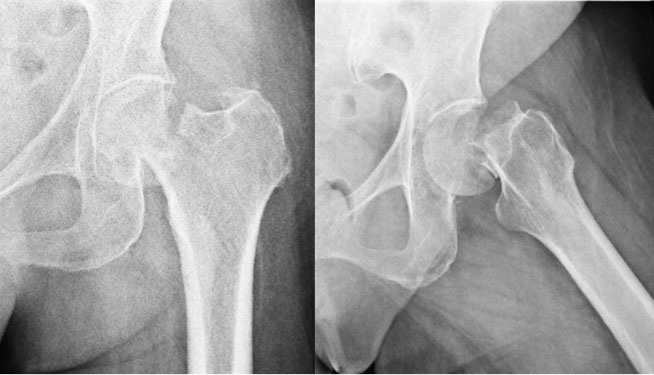

One of the causes of hip pain at night lying on the side is bursitis. Some of the issues that your therapist may identify as the cause of your hip pain when sleeping on either side include: This is considered one of the best positions for chronic back pain—and it can also do wonders for a bad hip.